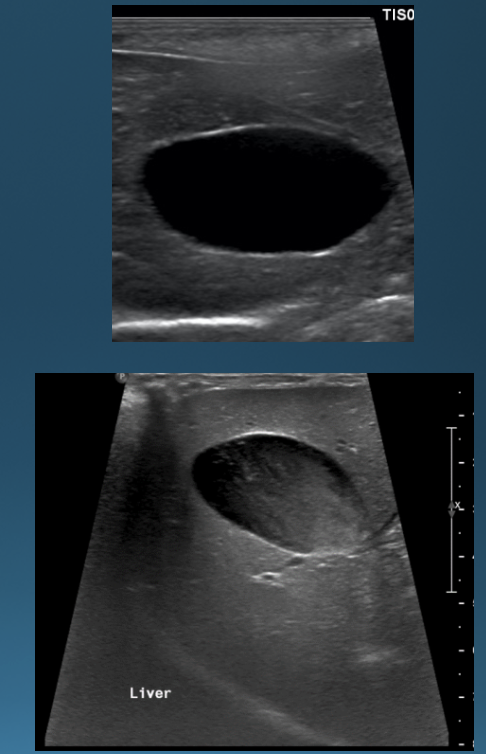

What is shown in these images?

normal ultrasound of the liver

What are the characteristics of the biliary tree on ultrasound?

-gall bladder typically contains anechoic bile

-presence of sludge is normal in dogs

-normally do not see intrahepatic bile ducts

-common bile duct is small; normally seen in cats

ultrasound of the gall bladder:

-top: anechoic bile

-bottom: sludge (normal in dogs)